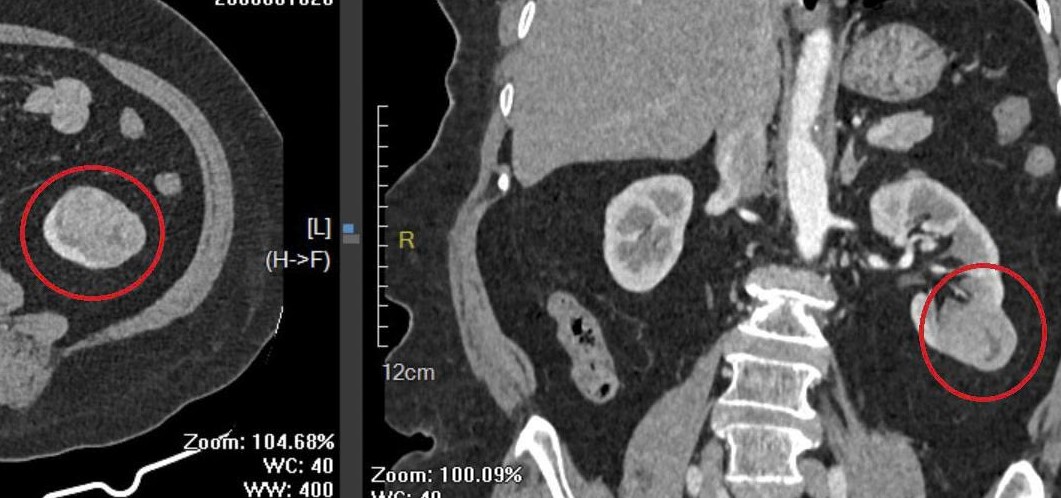

Sau khi hội chẩn và đánh giá toàn diện tình trạng sức khỏe, ê kíp điều trị thống nhất chỉ định phẫu thuật nội soi cắt một phần thận trái chứa khối u, đồng thời bảo tồn tối đa phần nhu mô thận lành nhằm duy trì chức năng thận cho người bệnh cao tuổi.

Ca phẫu thuật diễn ra thuận lợi, không ghi nhận biến chứng. Sau mổ, người bệnh hồi phục tốt, các chỉ số sinh tồn ổn định, chức năng thận được bảo đảm và được kế thúc điều trị vào ngày 26/1.

Khối u có kích thước 3x4x3 cm sau phẫu thuật. Ảnh: BVCC.